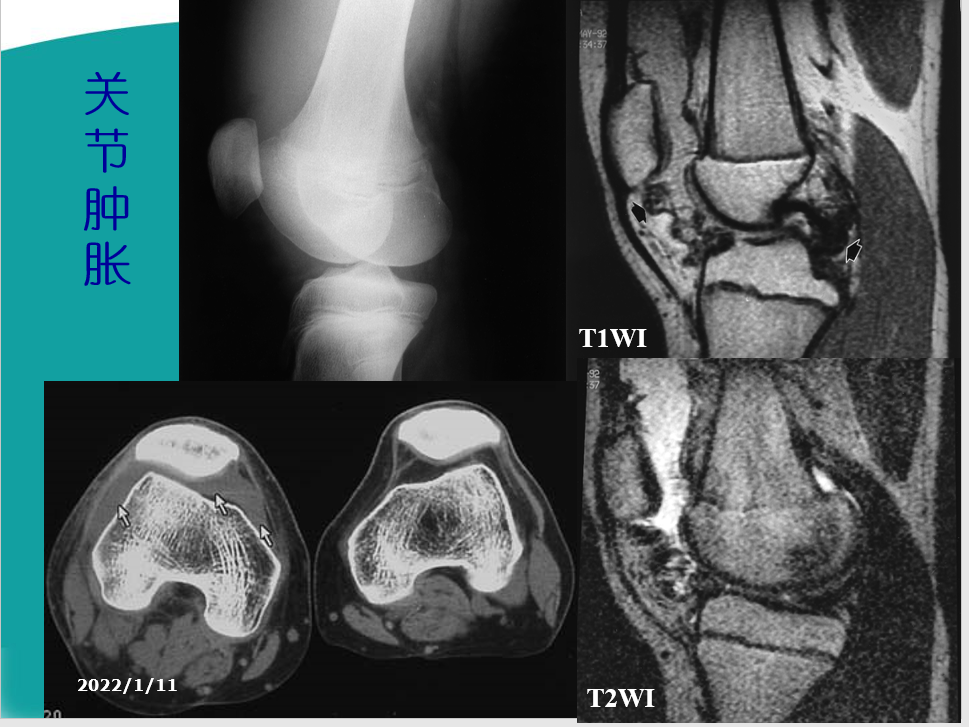

2.肿胀:部分患者关节肿胀,并反复发作。3.畸形:膝关节可出现内翻或外翻畸形,关节骨缘增大。有些患者不能完全伸直膝关节,严重者则膝关节呈屈曲挛缩畸形。4.功能障碍:运动节律异常:打软腿、弹响声、绞锁症。运动能力减弱:关节僵硬、不稳、屈伸受限、步行能力。

X线检查基本特征1.关节间隙变窄:成人膝关节间隙为4mm,小于3mm即为关节间隙狭窄,60岁以上的老人膝关节间隙为3mm,小于2mm为关节间隙狭窄。2.软骨下骨板硬化:软骨下骨板致密、硬化,负重软骨下骨质内可见囊性改变。3.骨赘形成

关节软骨的改变:软骨水肿、软骨囊性变、软骨变薄、磨损、软骨破坏